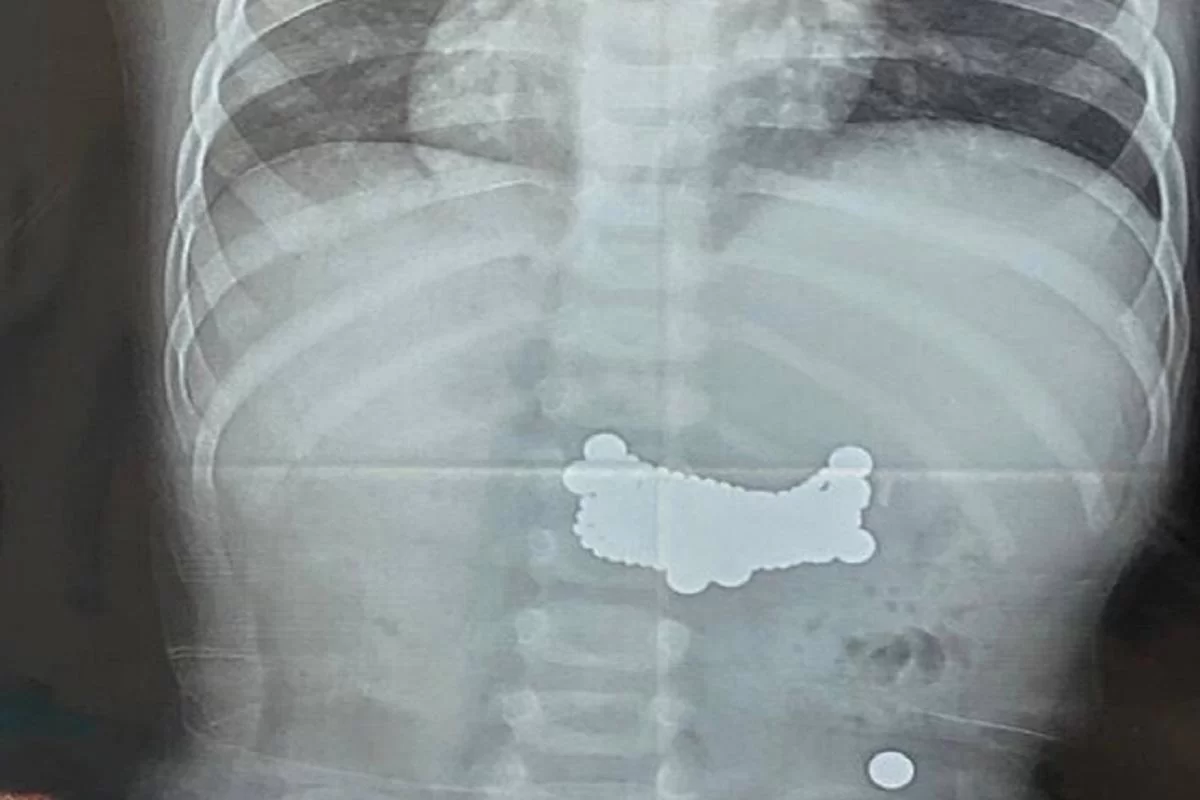

Во время томографического исследования врачи обнаружили множественные инородные тела, распределенные по всему желудочно-кишечному тракту. Как выяснилось в ходе дальнейшего осмотра, ребёнок ранее проглотил 11 небольших магнитов. По данным медиков, эпизод произошел задолго до госпитализации, однако мальчик из-за стеснительности и страха не сообщил о случившемся родителям.

Диагностика показала, что семь магнитов скопились в желудке, ещё четыре продвинулись в тонкую кишку. За время нахождения в организме магниты успели сцепиться между собой и повредить стенку желудка, что привело к перфорации и потребовало немедленного оперативного вмешательства.